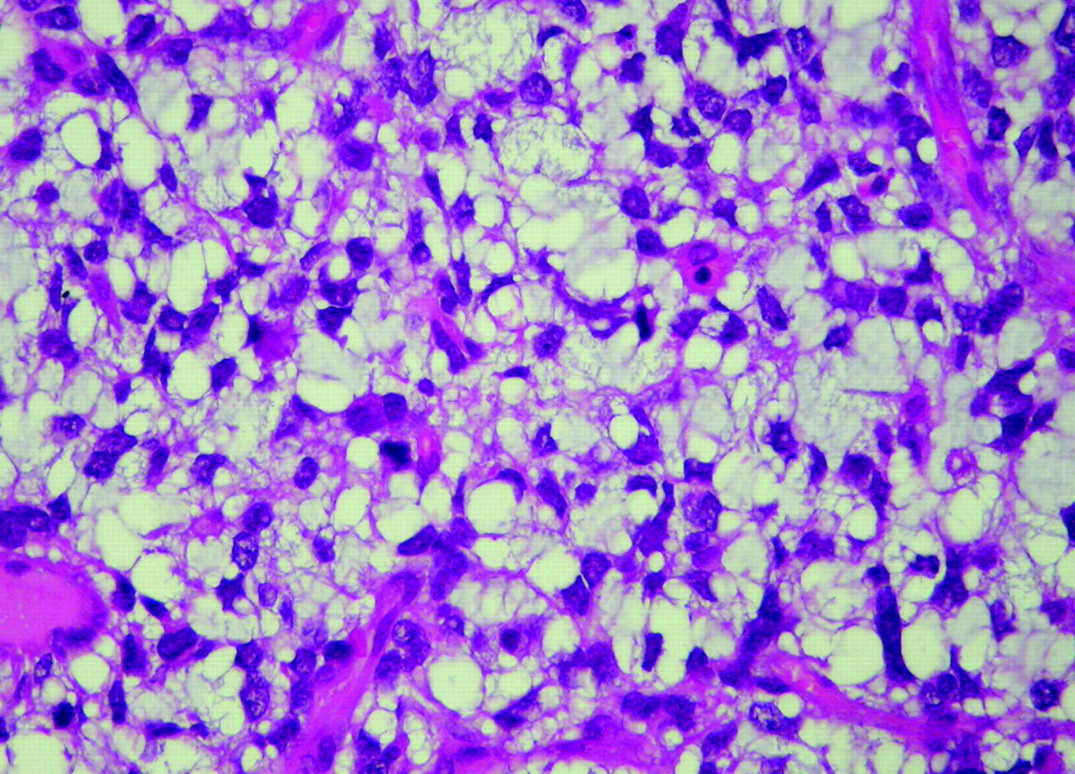

Микрофотографии гистологии глиобластомы головного мозга